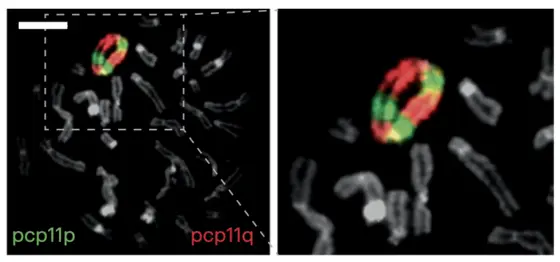

CK-AML: Chromosomen bilden sogar ringförmige Strukturen aus

Dies gilt nicht im gleichen Maße für alle Krebsarten. Besonders betroffen sind beispielsweise Patienten mit einer speziellen Form von Blutkrebs, der akuten myeloischen Leukämie mit komplexem Karyotyp (CK-AML). In den Chromosomen dieser Leukämiezellen herrscht enorme Unordnung: Abschnitte sind verloren, verdoppelt oder falschherum eingefügt. Experten bezeichnen diesen chaotischen Zustand als chromosomale Instabilität oder auch als „Chromothripsis“. Die Prognose der Betroffenen ist deutlich schlechter als die von AML-Patienten mit regelrechten Chromosomensätzen, da ihre Erkrankung oft auf keine der verfügbaren Therapien anspricht.